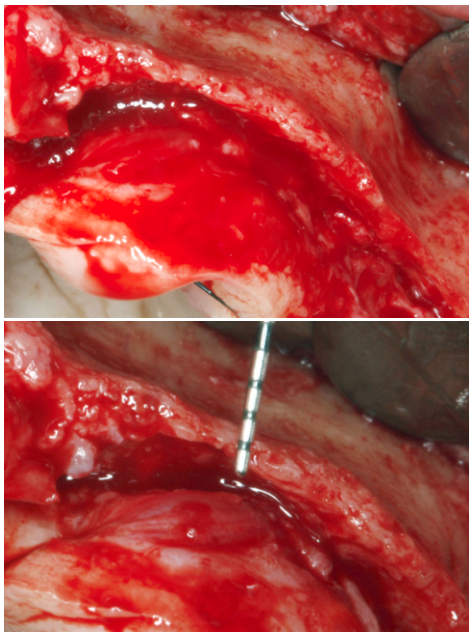

Una vez planificado el caso se procede a la cirugía de inserción de los implantes inferiores, superiores y las diferentes técnicas de aumento de volumen óseo descrito. Se comienza por la cirugía mandibular para obtener hueso autólogo obtenido del fresado que será conservado durante toda la cirugía en PRGF-Endoret fracción 2 sin activar, para ser utilizado en el maxilar donde será necesario para los injertos en bloque, según la técnica descrita por nuestro grupo de estudio19 (Figuras 7 y 8). Una vez obtenido el injerto en bloque será dividido y mantenido en PRGF-Endoret fracción 2 sin activar, para mantener su hidratación y viabilidad celular hasta su colocación según la técnica descrita por Khoury donde se utiliza la cortical del injerto en bloque como encofrado (Figuras 9 y 10)20 .

Finalizada la cirugía mandibular, se realiza la apertura del colgajo superior, donde se constata la gran atrofia en sentido horizontal que existe en determinadas localizaciones, anteriormente descritas, que precisan de la realización de injertos en bloque (Figuras 11 y 12). Se procede a la realización de la técnica de Split en dos fases (Figura 13) con la inserción de los implantes transicionales y la inserción de los implantes que podían ser colocados de forma directa. Una vez terminada la inserción de todos los implantes se fijan las corticales de los injertos en bloque, intentando ser adaptadas a la morfología residual lo mejor posible, evitando aristas que puedan dañar el tejido blando. Una vez fijadas, se rellenan los gaps con hueso autólogo particulado obtenido del fresado de los implantes inferiores, principalmente, así como hueso obtenido del raspado de la rama mandibular (Figuras 14-18).